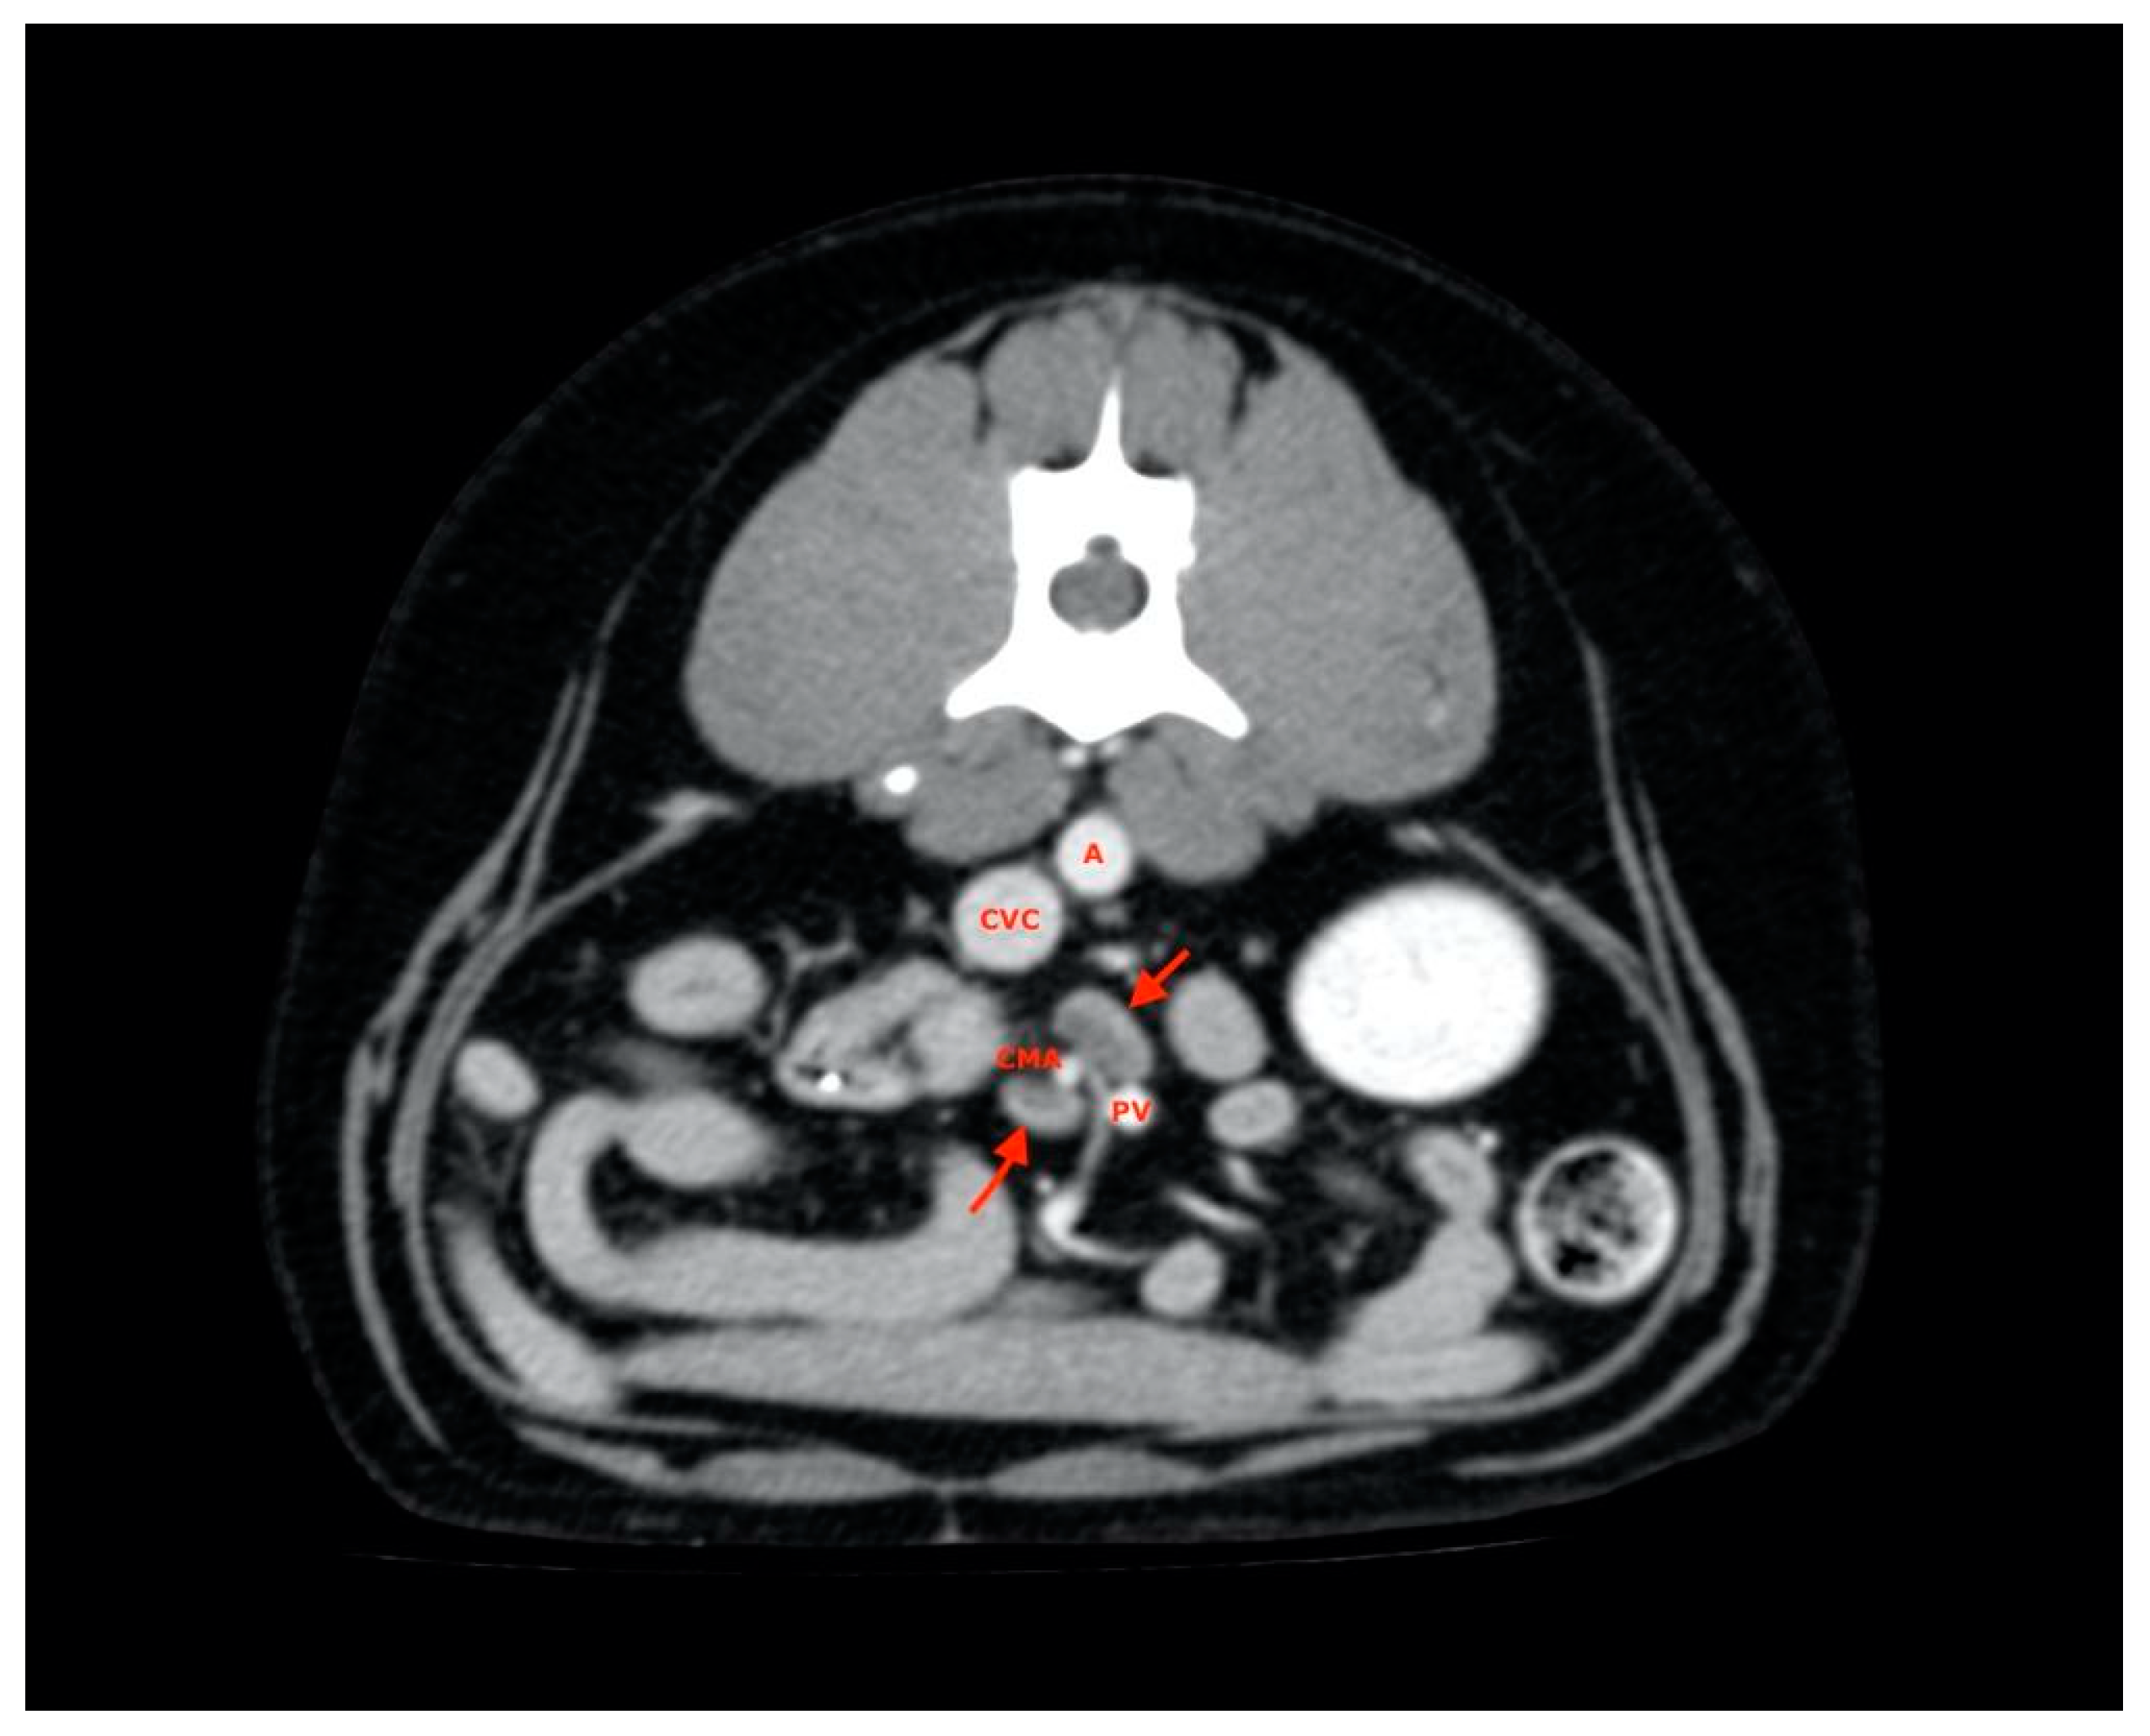

2.4. Procedures

2.5. Measurements